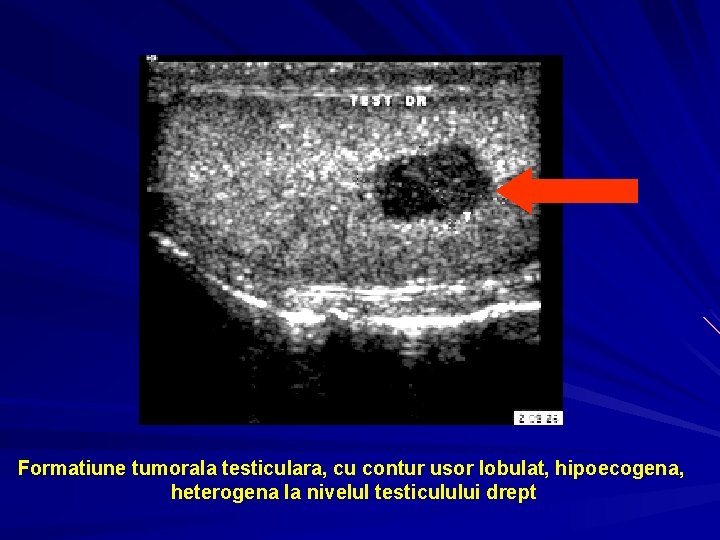

Formatiune tumorala testiculara, cu contur usor lobulat, hipoecogena, heterogena la nivelul testiculului drept